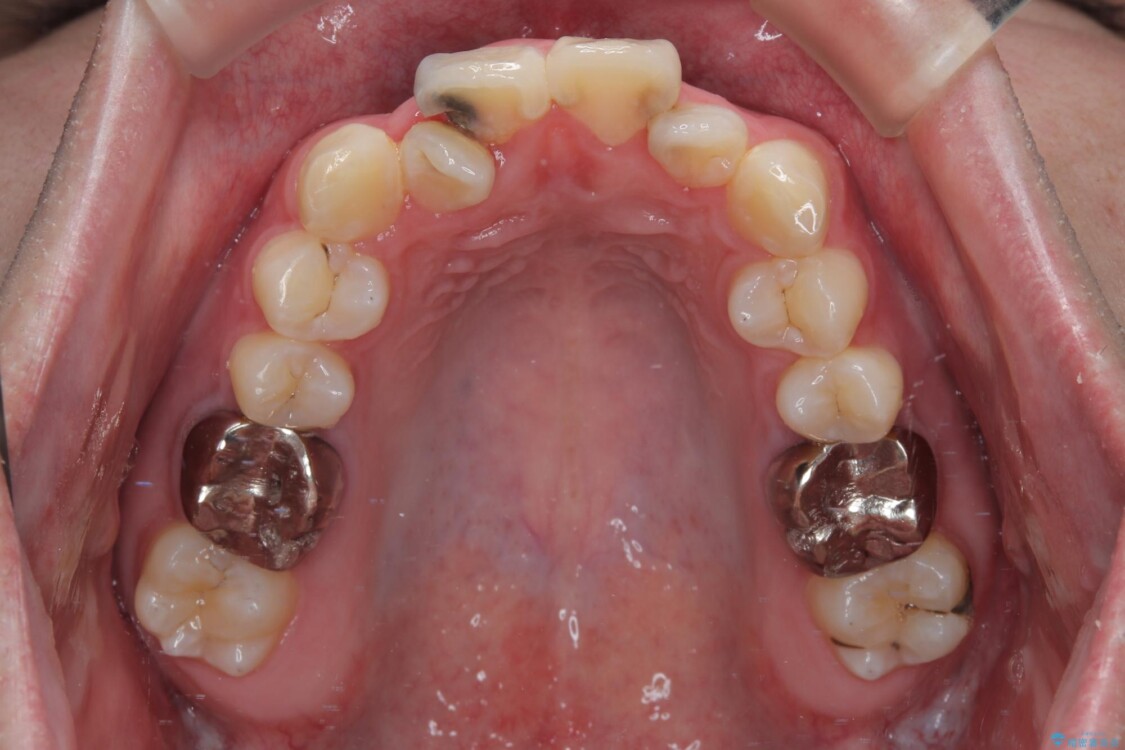

初診時の状態

・上下ともに歯がきれいに並びきらず、がたつきが見られました。

・上下の前歯の中心(正中)がずれています。

・特に上顎の幅が狭いため、下顎の歯列も内側に入り込み、歯が並ぶスペースが不足していました。

治療前

• 1年でここまで変わる!歯列のがたつきと正中のズレを改善した矯正治療(メタルブラケット×MARPE) 治療前画像